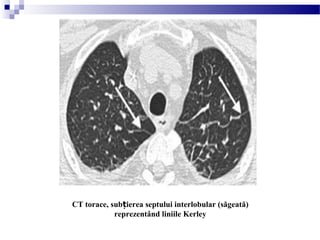

LINIILE KERLEY B

- sunt linii orizontale mai mici de 2cm lungime, de obicei la periferia zonelor

inferioare

- cauzele de apari ie a liniilor Kerley B sunt:ț

 edemul pulmonar

 limfangită carcinomatoasă i limfom malignș

 pneumonia virală i micoplasmicaș

 fibroză intersti ială pulmonarăț

 pneumoconioză

 sarcoidoză

- ele pot fi semne trecătoare pe radiografia toracică a unui pacient cu sau fără

insuficien ă cardiacăț

LINIILE KERLEY

B

Insuficien a cardiacă congestivă cu edem intersti ial; liniiț ț

Kerley B la periferia hemitoracelui drept.

CT torace, sub ierea septului interlobular (săgeată)ț

reprezentând liniile Kerley